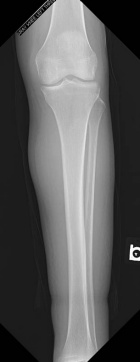

70 year old female with swelling of the left calf

Zoom image: Radiological image Radiological image.